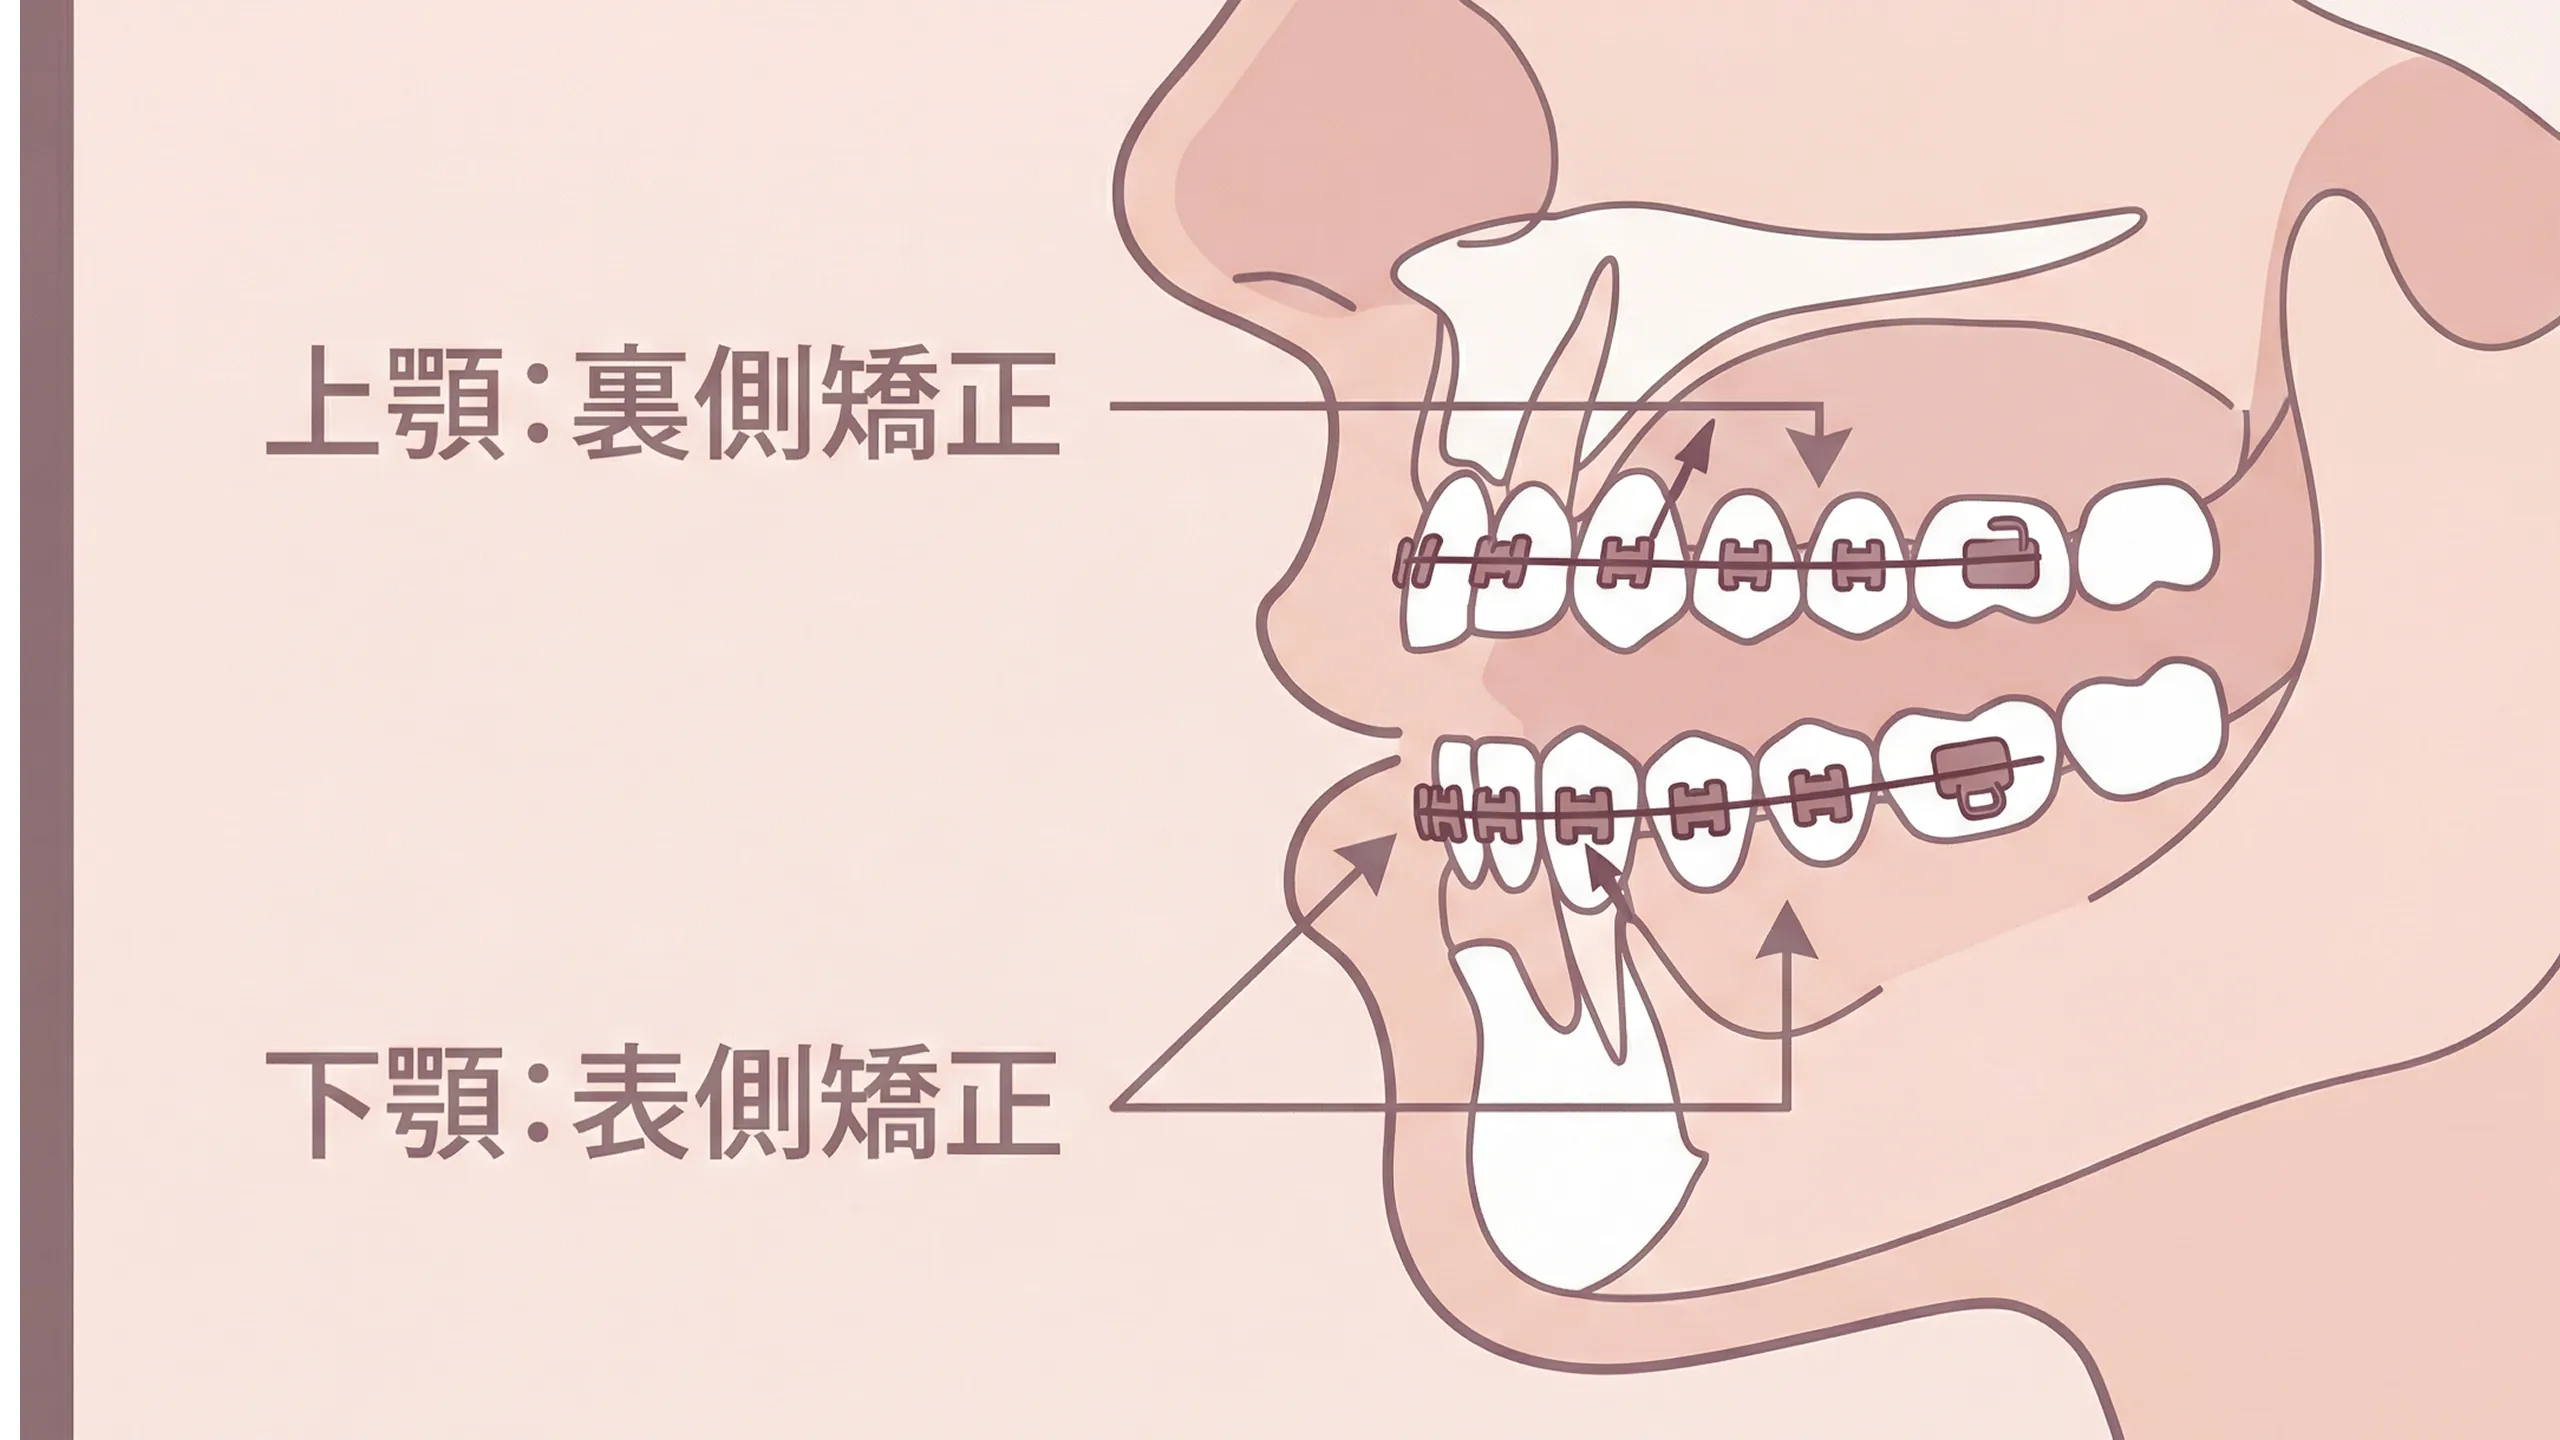

ワイヤー矯正装置

歯を立体的に動かすことができ、Ⅰ期後半やⅡ期治療の仕上げに適しています。目立ちにくいタイプのブラケットを使うことも可能で、前歯だけの部分矯正にも対応しています。

プラーク(歯垢)コントロールを重視し、染め出しやプロクリーニングを定期的に行います。痛みがある場合は、表面麻酔や電動麻酔を使ってできるだけ負担を減らします。